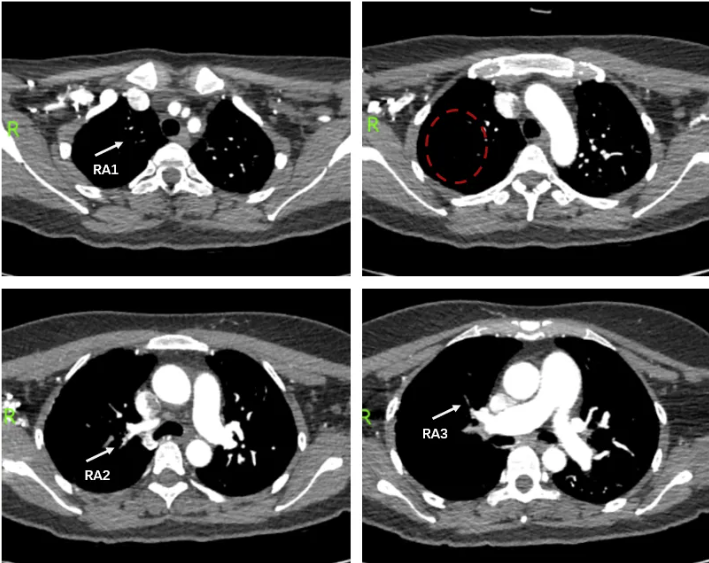

图5 2024.8.31 头颈联合CTA扫及上肺,RA1、RA2、RA3多发狭窄、闭塞,右上肺血管纹理稀疏。

追问患者胸闷病史,患者诉2年余前出现活动后胸闷,因不从事体力劳动而未在意。再次回顾患者3月前心外科就诊时的头颈CTA(扫及双上肺),可见右肺上叶肺动脉及分支多发狭窄、闭塞(图5),经过3个月抗凝治疗,对比此次CTPA无明显变化。结合患者右心衰竭的临床表现,超声提示右心增大、三尖瓣关闭不全、肺动脉高压,拟诊慢性血栓栓塞性肺动脉高压(CTEPH)。

右心导管检查结果示(图7):mPAP 47/16(26)mmHg,CI 3.2L/min/m2,PVR 4.7WU,SvO2:51.3%。肺动脉造影可见(图8):肺动脉主干增粗,双侧肺动脉及其分支广泛狭窄、闭塞病变,远端血流差,以RA1、RA2、RA3、RA4、RA5、RA10、LA4、LA5、LA8为著。据此,CTEPH诊断明确。